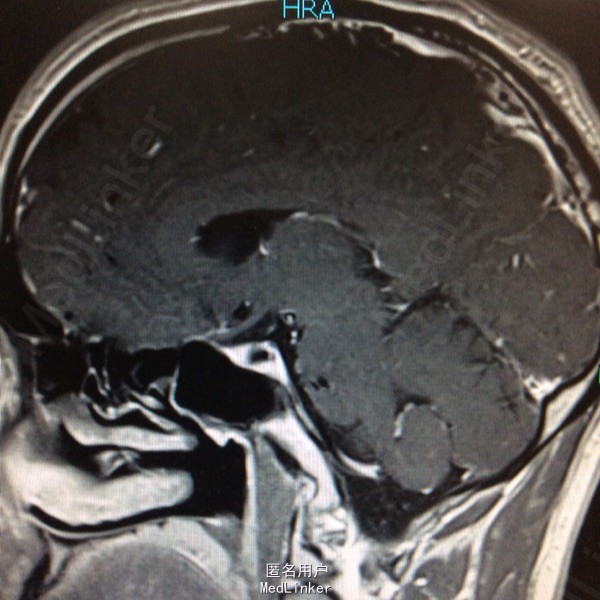

查体未见明显阳性体征,发育正常 头颅CT提示鞍区少量出血 MRI增强提示鞍区占位病变,大小约0.8*1.5cm 考虑垂体瘤卒中

术前诊断:垂体瘤 择期行经蝶入路垂体瘤切除术 术后病理提示垂体腺瘤